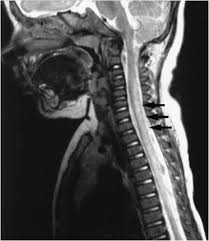

Transverse Myelitis This Is What The Spine Looks Like With Transverse Myelitis Neuropathy Treatment Neuropathy Treatment

Case Record Idiopathic Postinfectious Transverse Myelitis